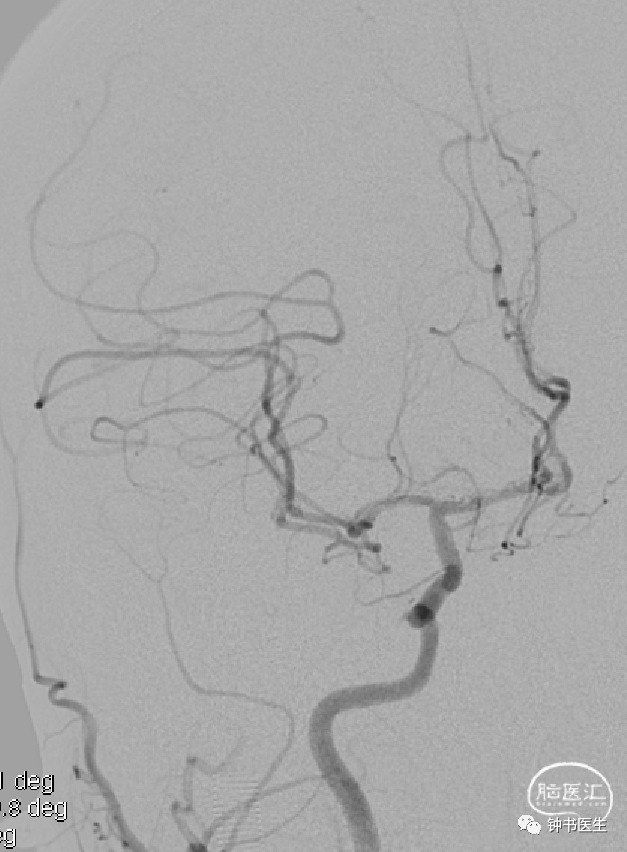

病例2

患者,女,78岁

突发右侧肢体无力5小时入院

高血压病20余年,予培哚普利降压。有糖尿病史4年,予阿卡波糖控制血糖。

BP:188mmHg/89mmHg

神清,语对答切题,右侧鼻唇沟偏浅,右上肢肌力2级,右下肢肢体肌力2级。

神经重症治疗思路

血压:超时时窗(降压)

原位狭窄(预防血压过低)

没有代偿(预防血压过低)

入院BP:188mmHg/89mmHg

目标血压:110-130mmHg

超时时窗(深度镇静镇痛)

原位狭窄(替罗非班、双抗)